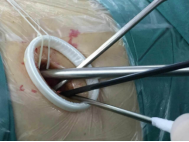

較兩孔、多孔胸腔鏡手術(shù)或傳統(tǒng)手術(shù),單孔手術(shù)具有創(chuàng)傷更小、出血更少、術(shù)后疼痛更輕、瘢痕小、切口更加美觀、術(shù)后恢復(fù)快、住院時間短等優(yōu)勢。但手術(shù)中所有器械(包括觀察鏡、吸引器、電凝鉤、切割閉合器、雙關(guān)節(jié)等各種操作器械)都要是從一個小“孔”進入,器械之間的互相干擾,同時器械與觀察鏡幾乎平行,視野非常狹窄,手術(shù)難度明顯,增加極其考驗醫(yī)生的技術(shù)。

器械進入小孔。